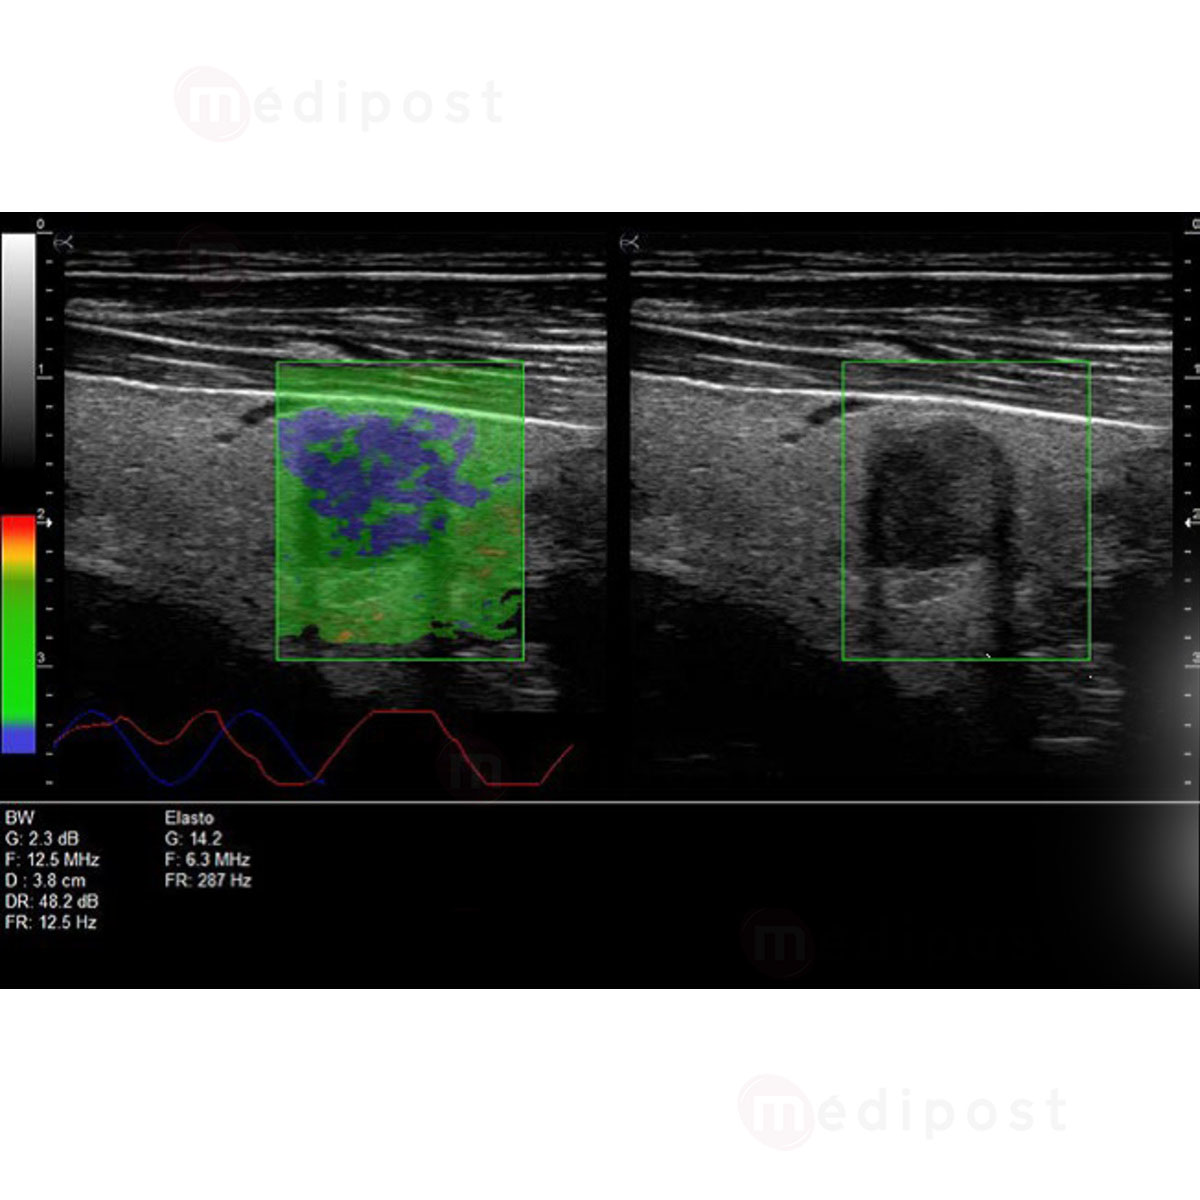

- Options Panoramique et Elastographie

- Elastographie pour une meilleure estimation du risque

- Sonde Linéaire HD Très haute fréquence 8-18 MHz (Parties molles, Vasculaire, Anesthésie, MSK, Médecine du sport, Pédiatrie)